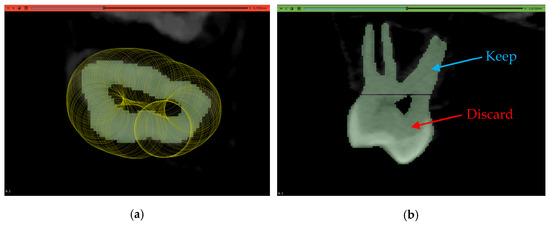

2.3.1. Volume Cropping

2.5. Workflow 2: GFS

2.6. Workflow 3: WS